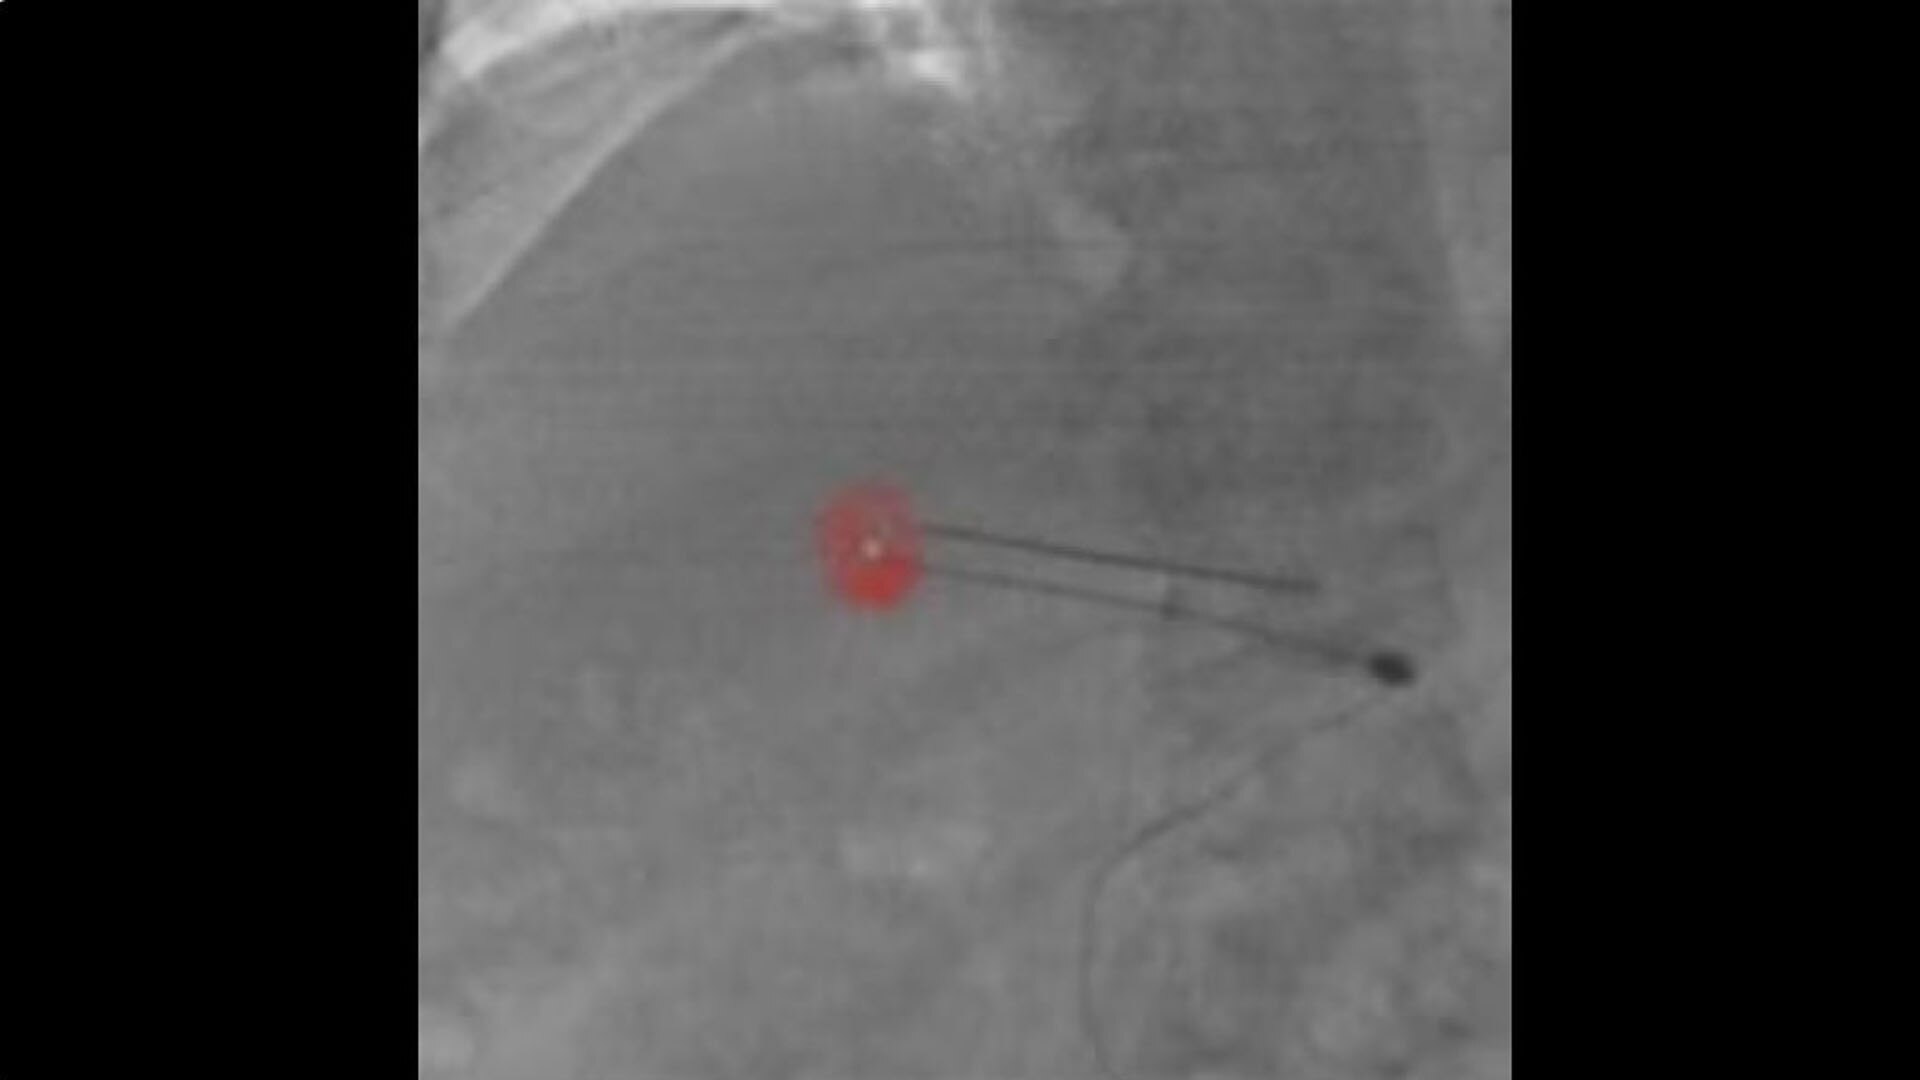

Access

Review needle placement

All at table side, reconstruct a needle in 3D with 2 fluoroscopic images with accuracy and to review the location of the reconstructed needle on the 3D anatomy.

hero_sticky_scrolling_3-ci-en